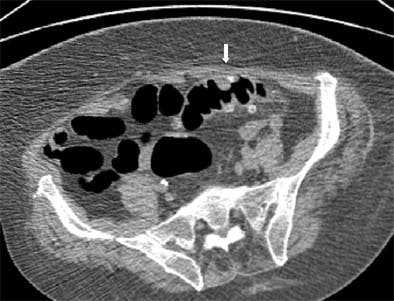

| Prone view: the sigmoid has flipped over its longitudinal axis, and better distension is obtained. A polypoid lesion remains visible (white arrow). Biopsy revealed only edematous mucosa and no polyp was detected. Images, courtesy of Dr. Philippe Lefere, were not included in the published study referenced herein. |

"On axial and (3-D) images, they present as a polypoid lesion, (and) the polyp-simulating mucosal prolapse syndrome is indistinguishable from actual polyps," the authors said. Appearing as a hyperemic mass, such lesions are also difficult to distinguish in conventional colonoscopy, and sometimes only biopsy and histology provides an answer, they added.